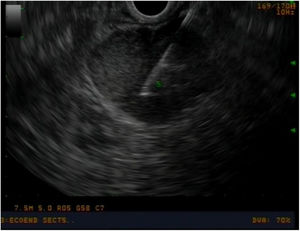

Estudio preoperatorio y seguimientoEn todos los pacientes se realizó un estudio preoperatorio exhaustivo mediante: tomografía computarizada (TC) toraco-abdominal, marcadores tumorales (cromogranina A, CA 19.9), perfil hepático completo, papiloscopia y ecoendoscopia para valorar las características de la ampolla de Váter y adenopatías locorregionales (Imagen 1) y realizar biopsias. En aquellos pacientes con duda diagnóstica (neoplasia ampular vs. coledocolitiasis vs. tumoración en cabeza de páncreas), se completó estudio con colangioresonancia magnética y octreoscan. En aquellos pacientes con ictericia o colangitis, se intentó evitar el drenaje preoperatorio de la vía biliar, con el objetivo de evitar complicaciones pre y posoperatorias14,15, así como riesgo de recurrencia16.